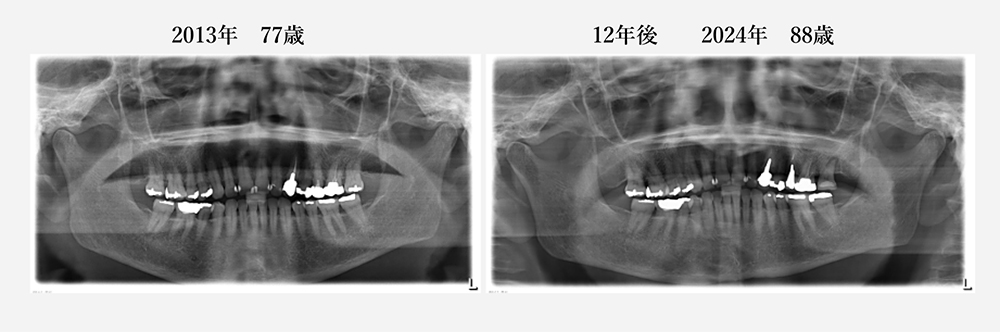

当院で20年以上メインテナンスをしていて、歯を抜くこともなく、

80歳を過ぎてもご自分の歯で美味しく食事ができています。

(デジタルレントゲン導入(2011年)後のレントゲン写真のみとなります)

現在88歳の女性